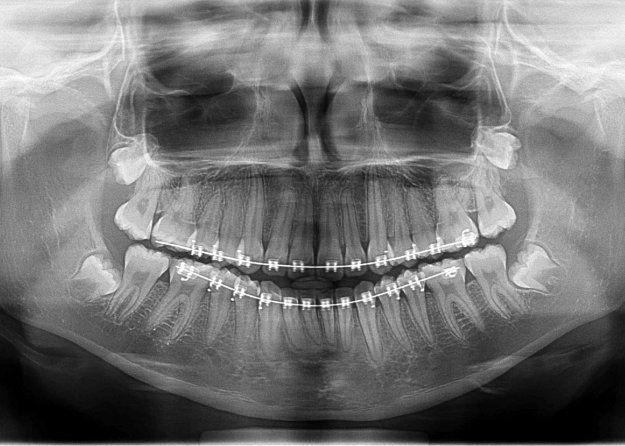

Técnica radiológica destinada a obtener una única imagen de las estructuras faciales que incluya las arcadas maxilar y mandibular, y sus estructuras de sostén.

Son una parte importante del tratamiento dental (tanto para adultos como para niños), ya que pueden detectar daño en los dientes y estructuras adyacentes  que no son visibles durante un examen visual de rutina.